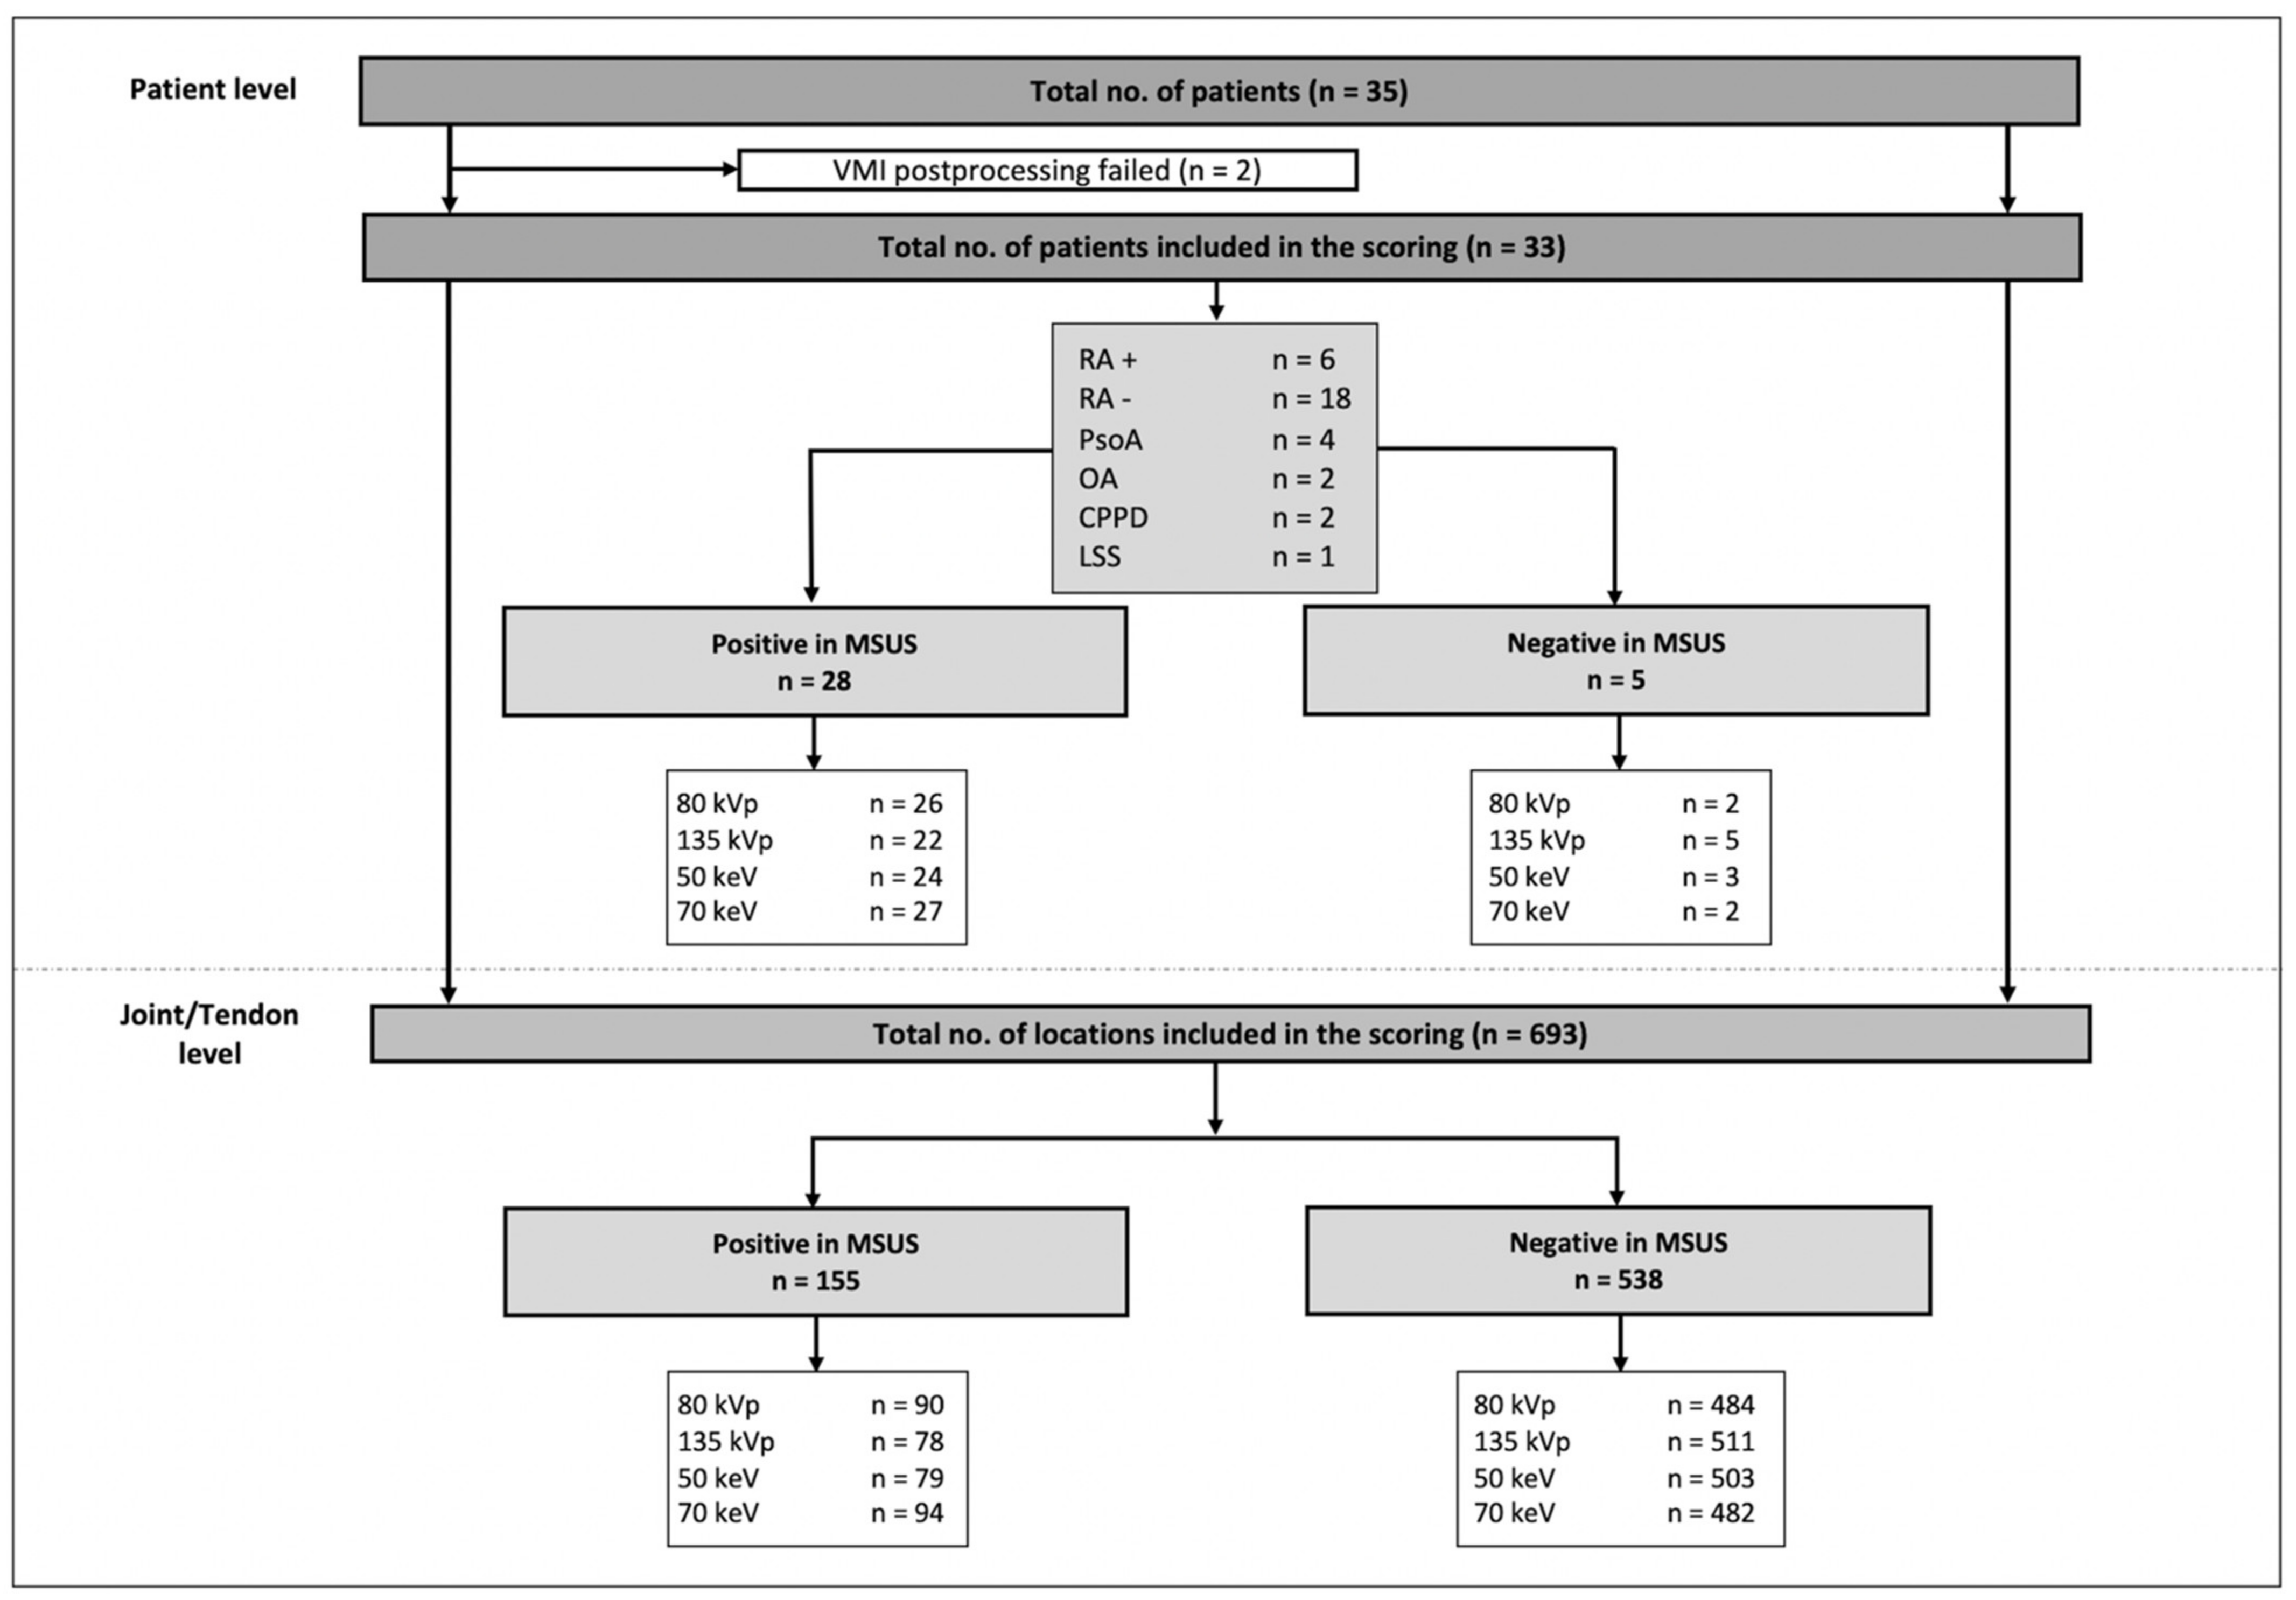

3.1. Subjects

3.2. Image Reading and Statistical Analysis